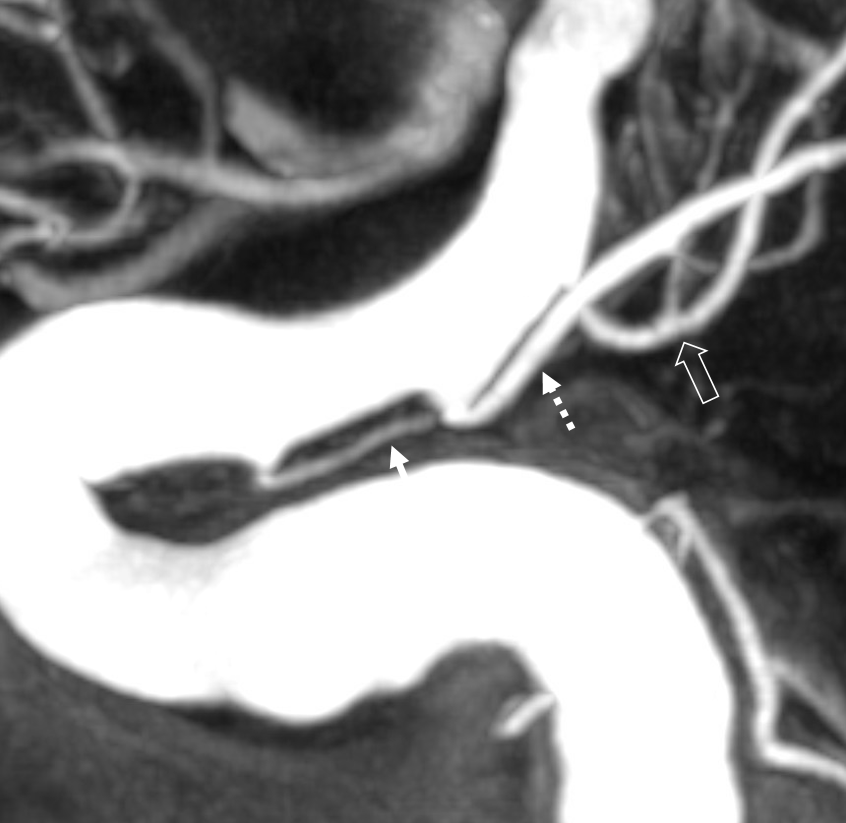

Supply of the Hypophysis and Balance

As always neuroangio is about balance. There may be one or more superior hypophyseal arteries. Usually one is visible by cone beam/flat panel CT. Sometimes more than two. Here there are 3. Nicely shown is supply of the stalk (open arrow). There is also likely contribution to the optic chiasm, which is of course very important. The inferior hypophyseal branches (dashed arrow) from the MHT support the posterior pituitary. The ILT is hypoplastic, with lateral branches of the MHT (white arrowhead) heading towards the meckel cave and the recurrent branch along the tentorial edge (black arrowhead) supplying territory normally done by the ILT

Without labels